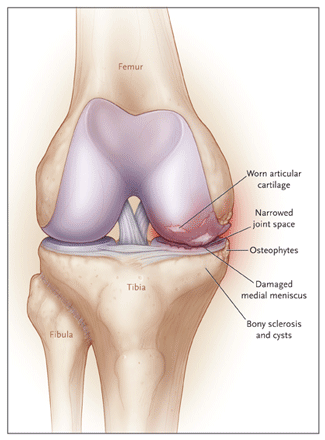

Knee Diagrams and my Cartilage Measurements

kneeDiagram-med

kneecDiagram2